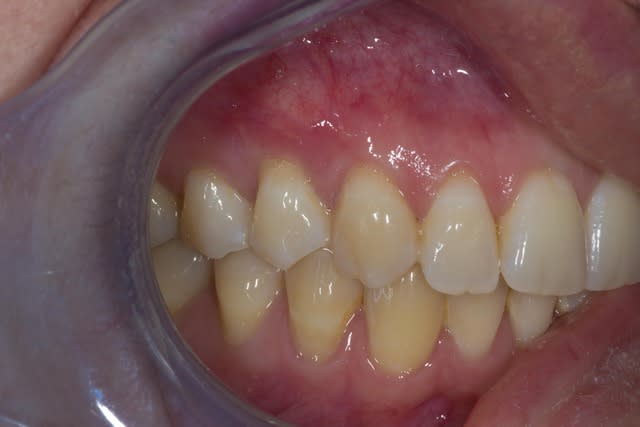

Comme on voit pas bcp de muco sur eugenol

P'tite 23 qui montrait trop de racine

Les 2 dernières photos sont à la dépose des fils (14 jours)